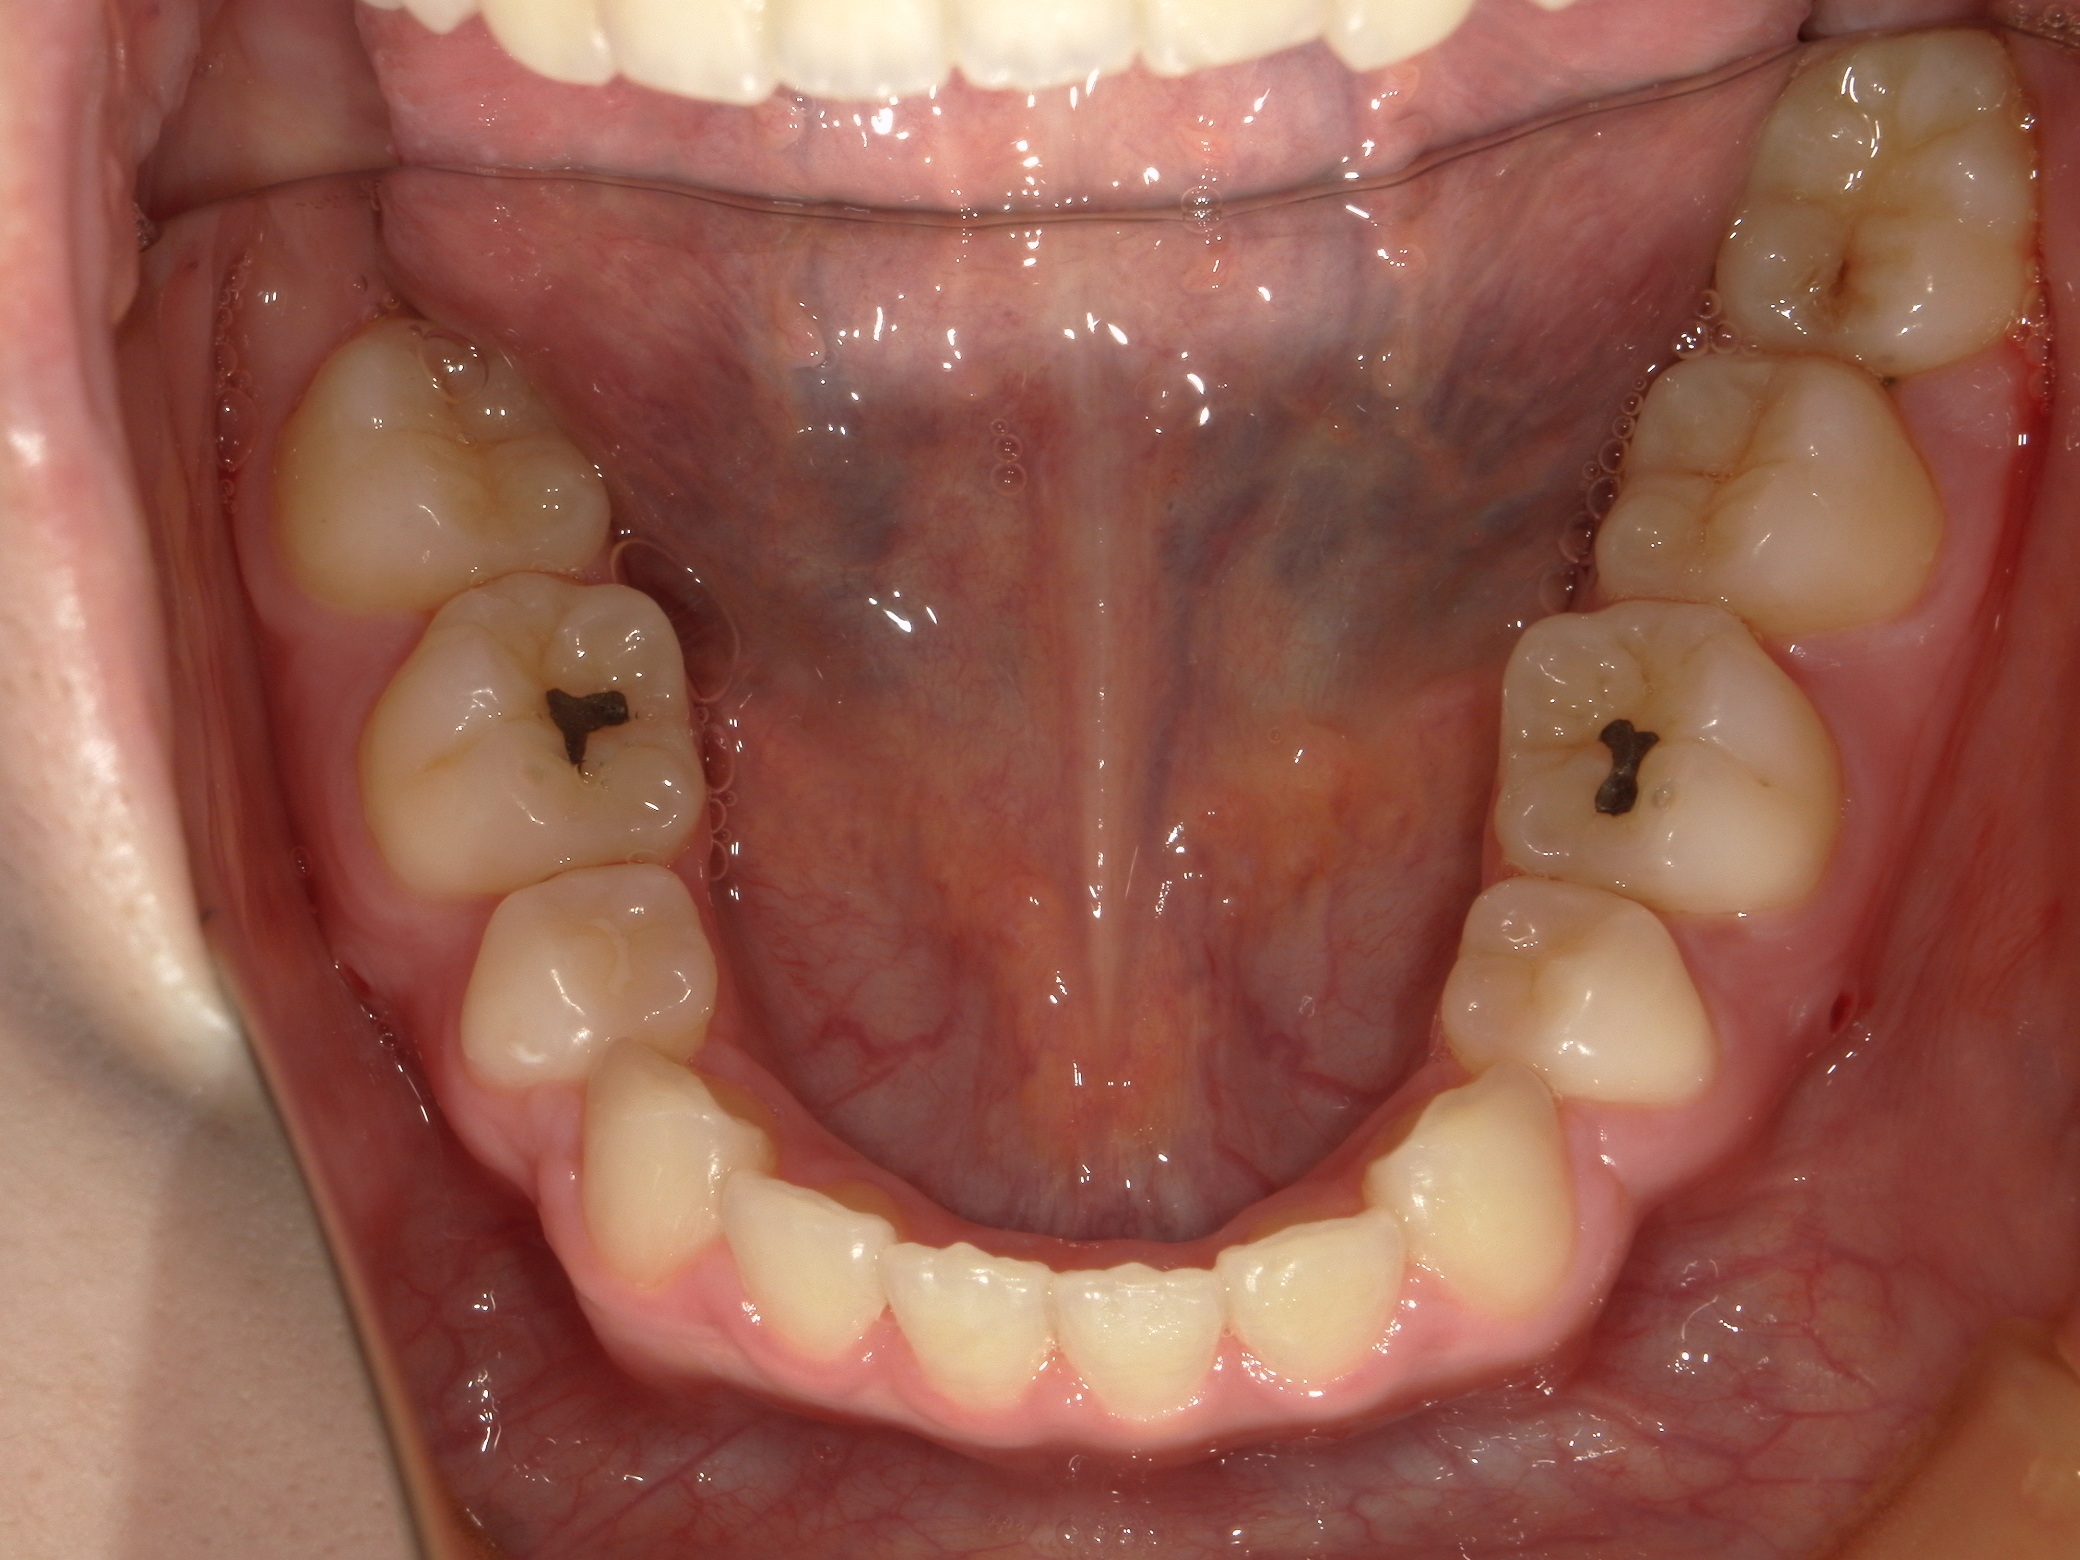

口内下

治療前

治療後

上の前歯に重なりがあることと口元が前突していることが問題となっていました。

上の前歯は唇側に傾斜しており、全体的に手前に倒れるような歯の配置となっていました

検査の結果、傾斜を治し、口元を内側に引き込むため、上下の歯を抜いてワイヤー装置で歯を並べることとしました

抜歯によって得られたスペースを十分に活かすことで、上の前歯の重なりと、口元の前突感、全体的な歯の傾斜を改善することが出来ました。